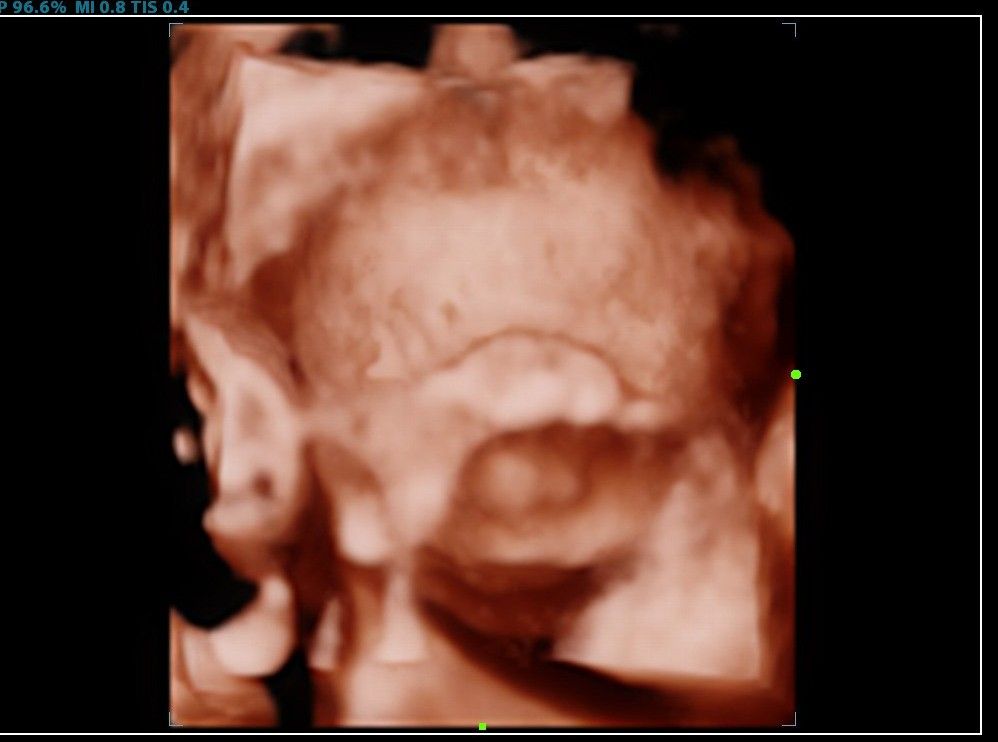

Вот ходили на скрининг, 31 неделя отлично лицо видно, в головном предлежании. Кто сказал, что вниз головой плохо видно?😄